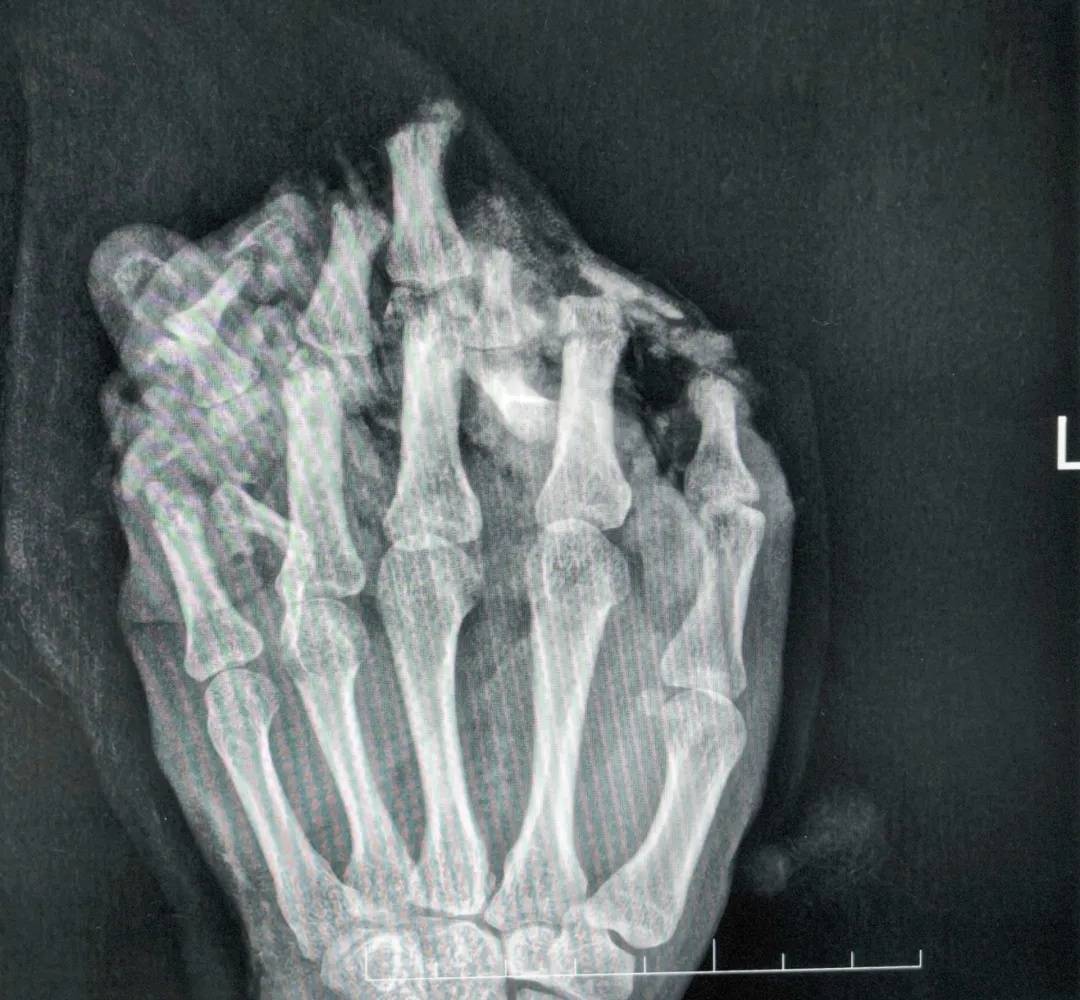

(拍片显示左手伤情严重)

医生诊断他为:1.左手掌、手背,示指中指环指小指掌侧及背侧皮肤毁损脱套伤;2.左手掌、手背及各指肌腱神经血管损伤;3.左手多发性开放性指骨骨折伴毁损;4.左拇指末节指腹皮肤、软组织缺损;5.左拇指指固有神经断裂;6.左拇指甲床裂伤。